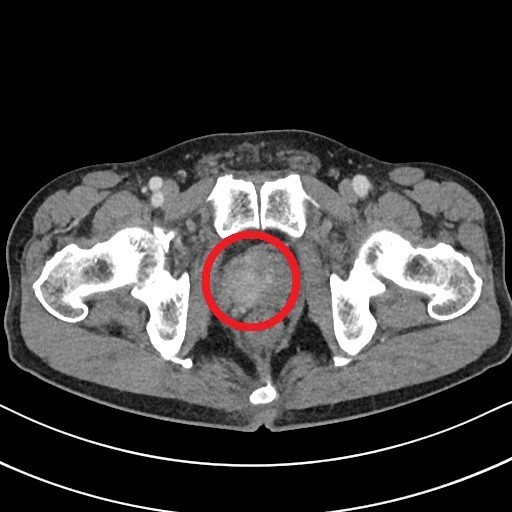

전립선암 원인, 초기증상 대해 알아보도록 하겠습니다., 전립선은 남자에게만 있는 장기로 정액의 일부를 생산하는 할 일을 해요. 전립선은 방광에서 나오는 요도를 둘러싸듯이 있으며 밤 열매와 같은 모양을 하고 있습니다. 전립선암은 이러한 전립선에 암세포가 발생을 한 것으로 50세 이후 60~70대에 많이 발생을 하는 남자만의 병입니다.

서양의 그럴 경우 전립선암은 남자암 중 가장 흔한 암으로 높은 발생 빈도를 보입니다. 우리나라의 그럴 경우도 최근 전립선암의 빈도가 급격히 높아지고 있습니다. 전립선암의 원인으로 가장 주요한 이유는 연령, 인종, 가족력입니다. 유전적 소인 외에도 호르몬, 식이생활습관, 제초제와 같은 화학약품 등도 발병에 주요한 요인으로 작용합니다. 전염성 질병, 성생활 정도, 사회경제적 상태, 정관수술, 흡연 등이 전립선암 발병에 영향을 미치는지에 대해서는 논란이 있으며 전립선암과 무관합니다.